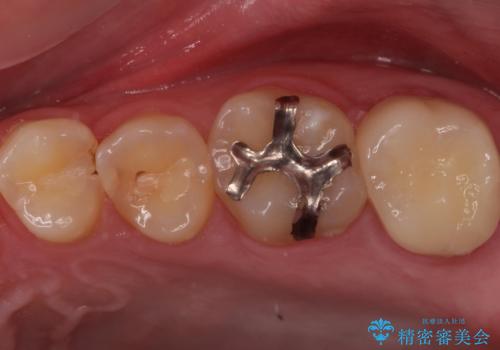

奥の虫歯 ジルコニアクラウンでの修復